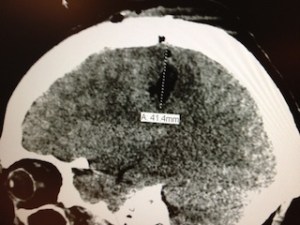

I got the diagnosis a couple weeks ago and have since been living the life of someone who has just found out they have brain cancer. My rockin’ neurosurgeon, Dr. Frank Coufal at Scripps Memorial in La Jolla, removed the large mass of it two weeks ago. I hung around ICU for about a week after that before I was released home. Since then, I have been meeting with the people who will make me all better. If you’re into the specifics of these types of things— it’s a grade 3, primary brain tumor called Anaplastic Astrocytoma, an aggressive type of brain cancer in my left frontal lobe. As a side note: that’s the area that controls speech, not optimum when you make your living as a San Diego Anchorman. Thankfully, I only lost my speech for a short while. The doctors tell me I have between 1 and 3 years to live.

P.S. Here are photos of my brain before and after the surgery. Pretty cool, huh?

[Above: Before Surgery/Below: After Surgery]